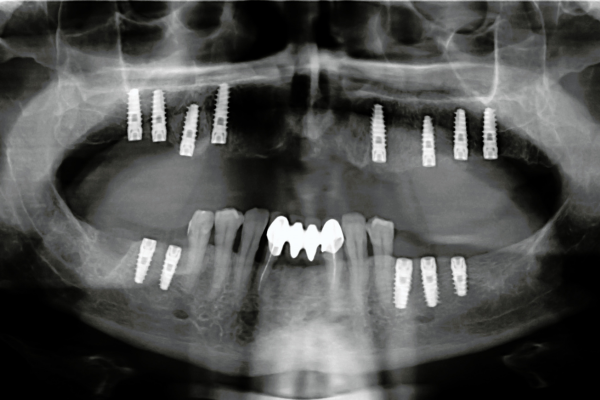

インプラント治療:機能と見た目を両立する精密な補綴

サイトウ歯科では、インプラント治療においても安全性と精度にこだわった対応が行われています。院内にはCT設備が整っており、術前の診断から施術まで、詳細な骨の状態や神経の位置を把握したうえで治療計画を立てることが可能です。

さらに、治療に使用する人工歯は、担当ドクター自らが手作りするハンドメイド方式を採用。患者様一人ひとりの噛み合わせや顎の状態に合わせて調整されるため、見た目の自然さだけでなく、機能面でも高い適合性が得られます。

使用素材もこだわりがあり、天然歯に近い弾力を持つ被せ物や、金属アレルギーのリスクを抑える貴金属などを選定。これにより、咬合バランスを損なうことなく、長期的な安定性を追求したインプラント治療が可能となっています。審美性・耐久性・安全性の三要素を兼ね備えた、高品質な補綴治療が提供されています。